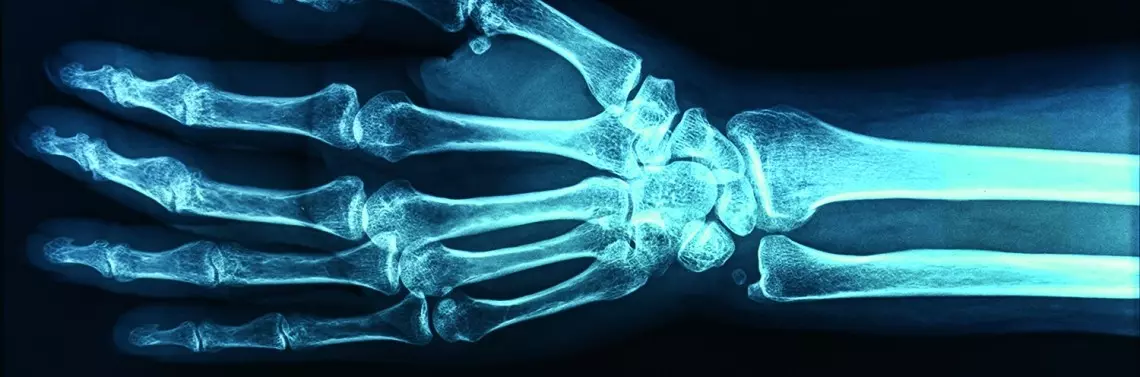

Fizjoterapia urazów stawu nadgarstkowego u narciarzy i snowboardzistów

Popularne obecnie narciarstwo i jazda na snowboardzie wiążą się z niebezpieczeństwem upadku, a co za tym idzie − ryzykiem powstania urazu stawu nadgarstkowego. Niestety wiele uszkodzeń nadgarstka jest nieprawidłowo rozpoznanych bądź nierozpoznanych, a tym samym niewłaściwie leczonych. Ogromne znaczenie dla odzyskania pełnej sprawności ręki, która uległa urazowi, ma postępowanie rehabilitacyjne.